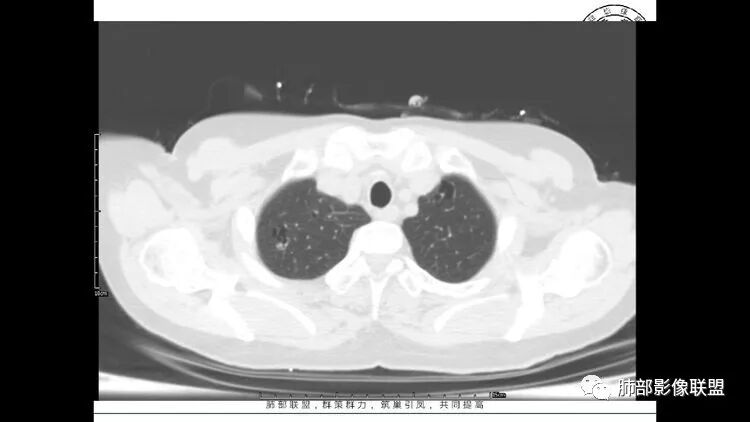

老年女性,长期使用激素史。双肺多发散在斑片状磨玻璃密度影及大小不等的薄壁含气囊腔,下肺相对较多较大。双肺多发结节,左肺上叶结节相对较大,界清,边缘光滑,分叶不明显。右肺下叶前外底段散在树丫。前上纵膈偏左侧不规则软组织团块,颗粒感,偏软。肺内囊腔及磨玻璃影考虑淋巴细胞间质性肺炎,或淋巴管肌瘤病。纵膈团块考虑淋巴管瘤。两者结合,考虑淋巴细胞增生病变。右肺下叶散在树丫,结核待排。双肺结节性质待定。

老年女性

自己滴眼2年,提示病史比较长,可能炎症?干燥?

小叶中心囊+结节,中央间质增厚

GGO

前纵隔结节,附近小淋巴结

常规:小叶中心囊+结节,女性

LIP、LAM、LCH、BHD、恶性肿瘤

LAM:一般无结节

LCH:肋膈角区少,男性、吸烟史,不支持

BHD:家族史,皮肤、肾脏,囊一般较大,胸膜下为主

LIP:小叶中心囊+结节+间质改变;如果实变病灶较多,警惕淋巴瘤

恶性肿瘤:部分囊过于光滑,无壁结节,放待排

因此:LIP放前面